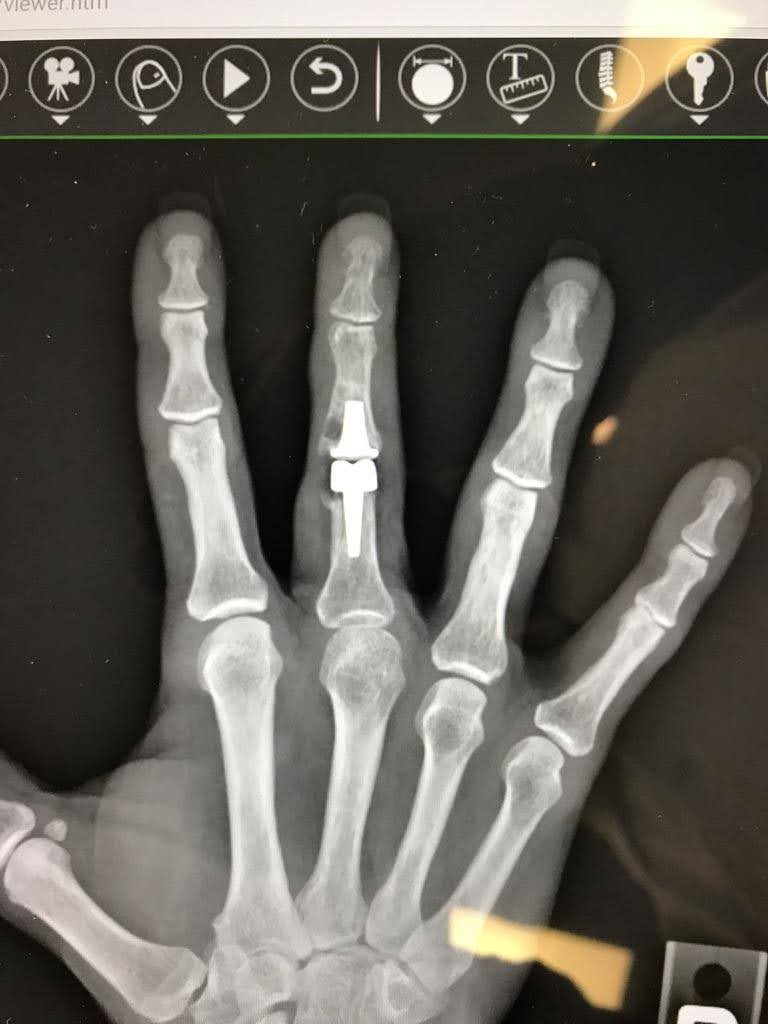

Revision Total Joint Arthroplasty from a silicone implant to cemented surface replacement arthroplasty (SRA)

Finger Joint Arthritis and Joint Replacement Arthroplasty – Case 2: